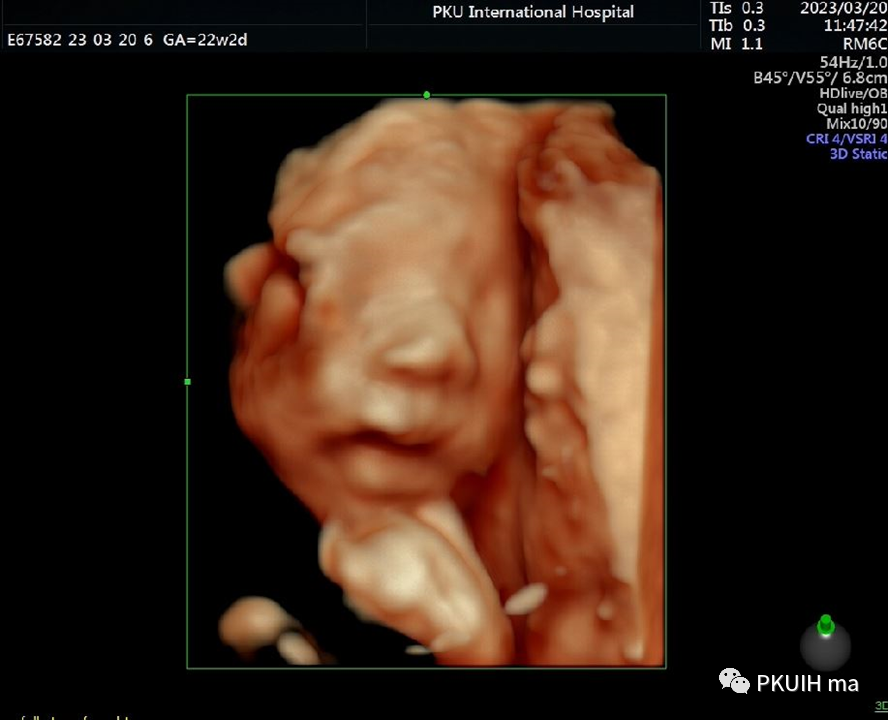

同样孕周大小胎儿做了三维图像显示热指数和机械指数分别是0.4、0.8并没有大于二维超声图像。同样下图三维超声热指数和机械指数是0.3和1.1,热指数也是很低的

小宝宝在打哈欠

在想美事

在思考或者是安静的休息